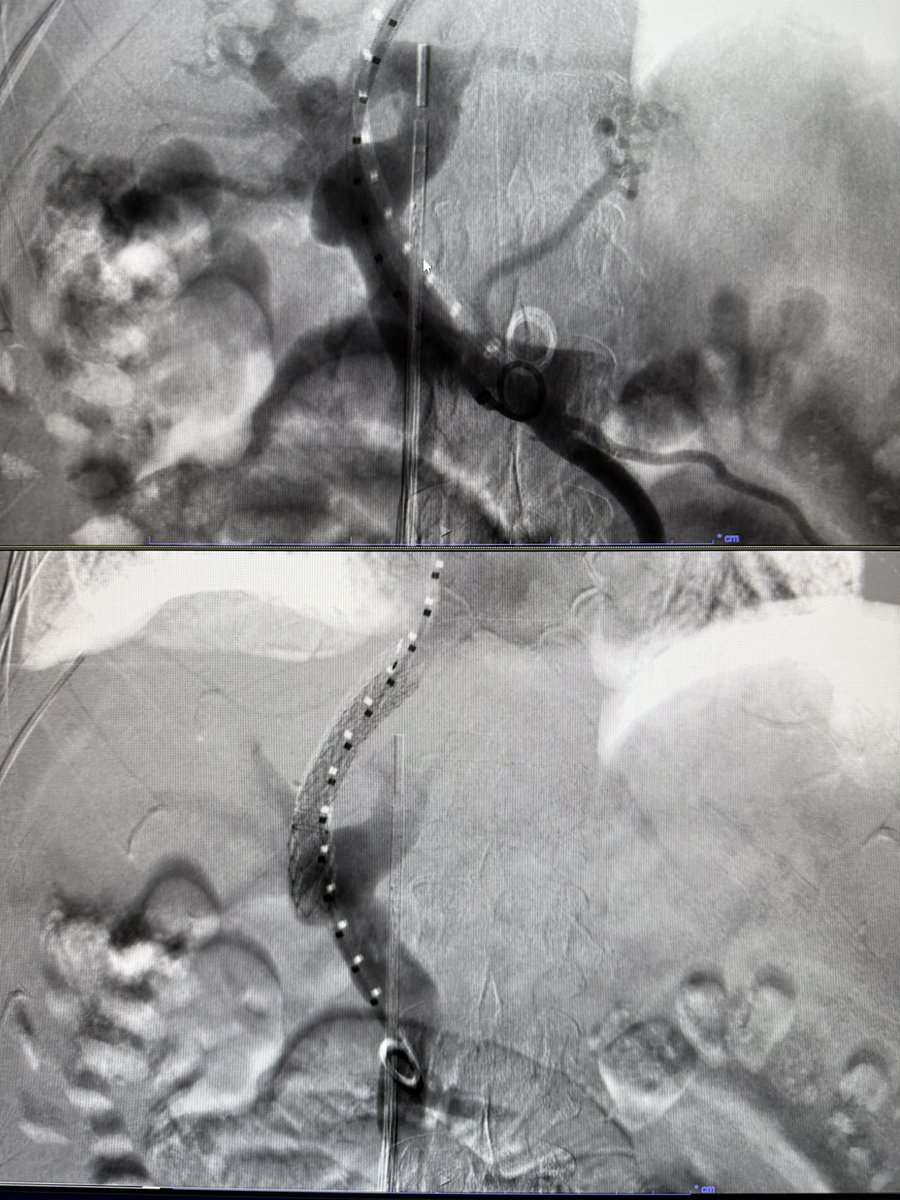

4 TIPS this week, 3/4 with moderate sedation, all under 30 mins to stent deployment. ICE and steerable needles are the future!